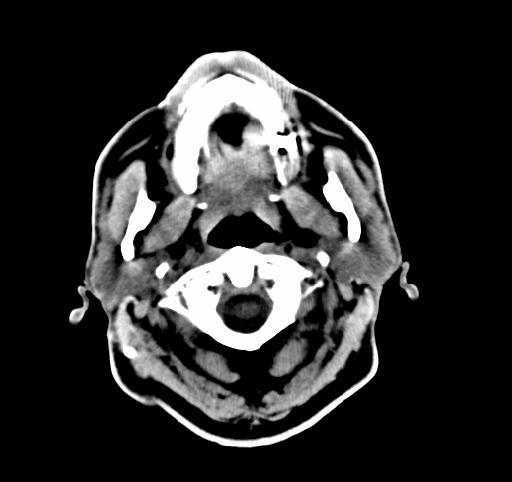

Each frame in the animation below is one such reconstructed slice:

For understanding the reconstruction algorithm, it is enough to focus on one slice at a time. We can idealize the problem as purely 2D: given many 2D projections of a single cross-section, how do we reconstruct the 2D density inside that slice? Details such as table motion or the stepping between slices do not affect this basic 2D reconstruction model.